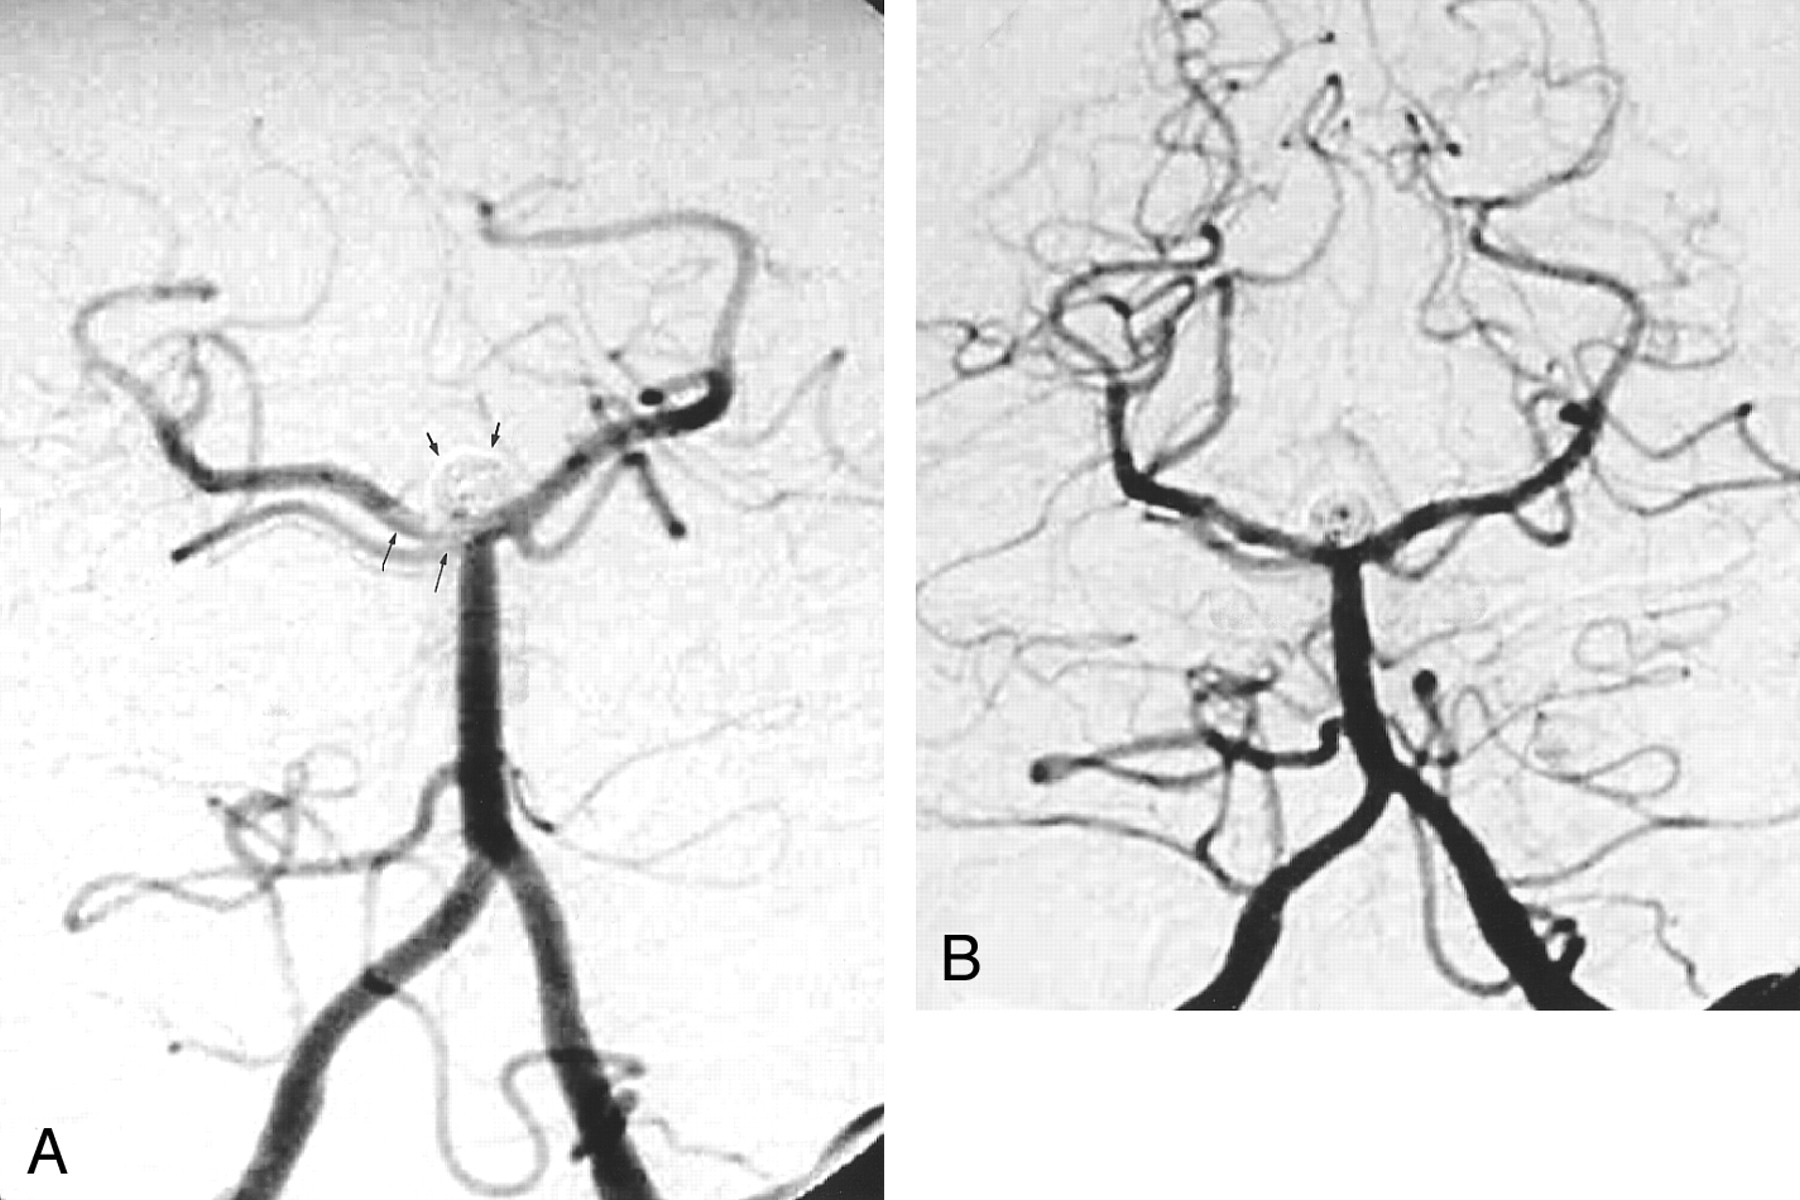

Images from the case of a 49-year-old male patient with a basilar tip aneurysm.

A, Angiogram of the left vertebral artery, transfacial projection. The basilar tip aneurysm is packed with GDCs (short arrows). A linear filling defect with hazy margins, consistent with thrombus, is present in the distal basilar artery and extends into the right P1 segment (long arrows).

B, Angiogram of the left vertebral artery, transfacial projection. After 24 hours of heparin infusion, follow-up angiogram obtained after GDC treatment shows resolution of thrombus. However, there is partial recanalization of the aneurysm centrally.